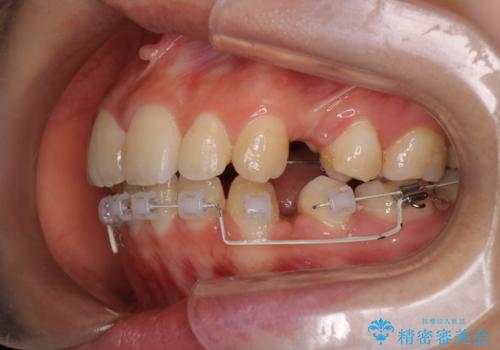

【ハーフリンガル】口元を下げたい!

- ハーフリンガル

- 口元が出ていることを主訴に来院されました。

歯を抜いてスペースを作ることで、前歯を下げることができました。

ハーフリンガルということで治療期間が3年近くかかりましたが、口元もしっかり下がり満足していただきました。